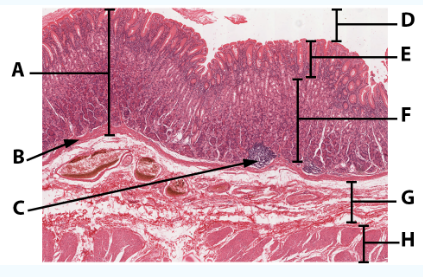

A

Mucosa

B

Muscularis mucosa

C

MALT

D

Lumen

E

Gastric pits: simple columnar epithelium

F

Gastric glands

G

Submucosa

H

Muscularis externa: oblique, circular, and longitudinal

area

Stomach